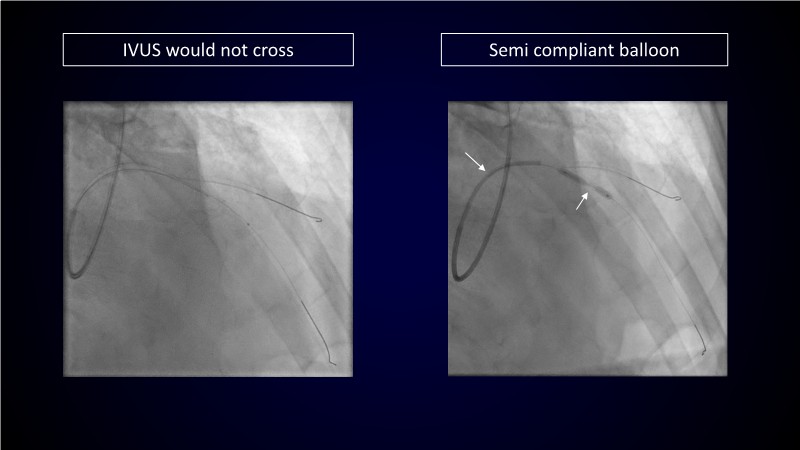

Calcified coronary lesions are a major challenge in PCI. This PCRGulf-GIM 2025 session showcases a complex case with intravascular imaging, highlighting how IVUS 123 guides each step.

From planning the procedure and understanding calcium distribution, to lesion preparation with modern modification tools, and post-PCI assessment to confirm stent expansion and detect complications, this session demonstrates practical, imaging-driven strategies.

Learn how careful preparation and modern techniques improve outcomes in treating severe calcium, calcified nodules, and in-stent restenosis.